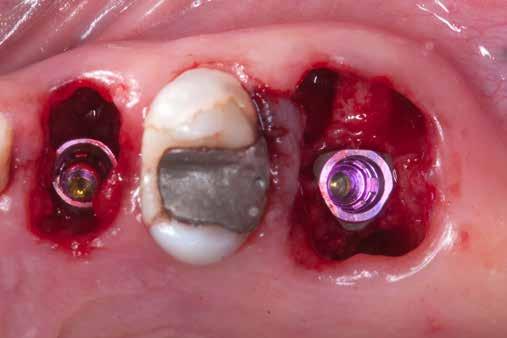

4. ábra: A fogszerkezet helyreállítása és a fogrestaurációs komplexum ellenálló képességének javítása érdekében ortodontikus extrúziót végeztek a szomszédos fogakra ragasztott drót és egy egyszerű rugalmas ligatúra segítségével.

5. ábra: Az extrudálás nyomon követése néhány hét múlva. Az extrúzió végén a lágyrészek kisebb mértékű újrakontúrozása történt. A szerző általában fibrectomia nélkül végzi az extrúziót, és az extrúzió végén a lágyrészek újrakontúrozását végzi.

6. ábra: A fog az extrúzió és a függőleges preparálás után. A függőleges preparáció a legjobb preparátum a fog szerkezetének megőrzése szempontjából, különösen akkor, ha minimálisan invazív megközelítéssel alkalmazzák. A szerző egy módosított vertikális technikát alkalmaz, amely nagyobb hangsúlyt fektet a pericervikális dentin fenntartására.

7. ábra: A bukkális szerkezet összehasonlítása extrudálás előtt/után . A maradék fogazati struktúra okklusális terhelése most sokkal kedvezőbb a hosszú távú eredmény szempontjából .